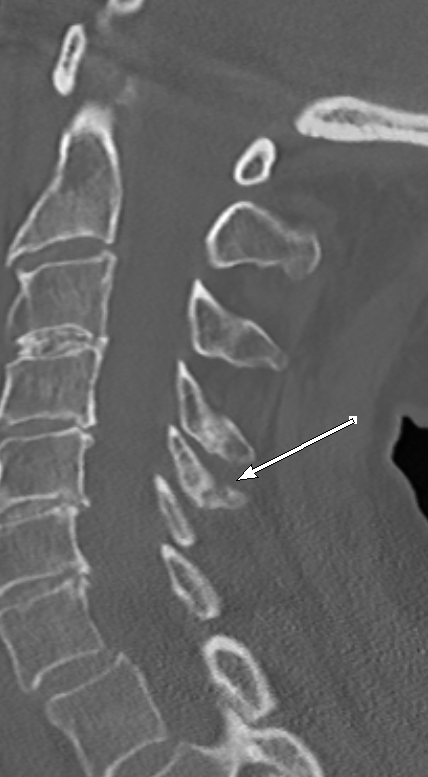

#easytomiss fracture of a bifid spinous process#spine#trauma#radiology#radres This fracture can be overlooked if you are focusing only on sagittal images#EMRad#FOAMrad#FOAMed@NASSspine https://bit.ly/32bT4VX pic.twitter.com/b0g3MRwzhf